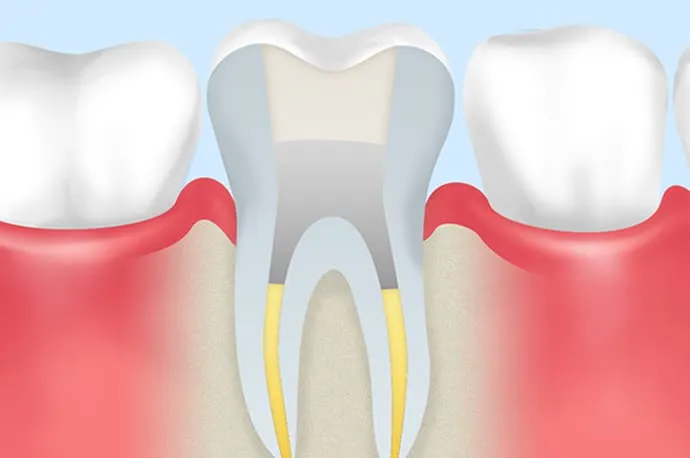

3.きれいな根管を維持する

根管内を清潔な状態にできたら、その環境を長く保つことが重要です。防腐作用のある材料やバイオセラミック系の糊材で根管内をすき間なく満たし、再び細菌が侵入しないようにします(根管充填)。

根管充填と土台作り

再来院時に問題がなければ、根管内に防腐剤の詰め物を行います(根管充填)。その後、感染を防ぐため、歯と強力に接着するレジンなどの材料で上からフタをし、歯の土台を作ります(築造)。